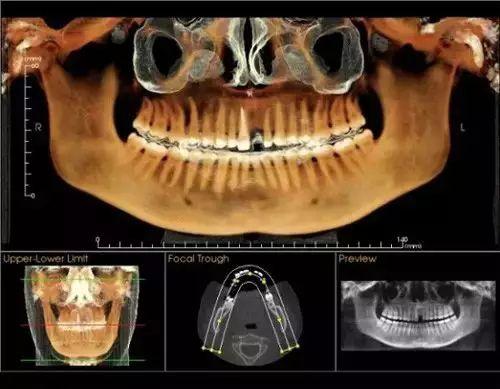

卡瓦錐形束多功能口腔CT(簡(jiǎn)稱CBCT),現(xiàn)已正式投入使用。CBCT是目前國(guó)際先進(jìn)膠評(píng)商的口腔科專用CT,在業(yè)界被譽(yù)為神奇的"慧眼",具有掃描快、范圍大、精度高、應(yīng)用廣、放射劑量極低的特點(diǎn)??梢酝ㄟ^(guò)其強(qiáng)大的處理軟件功能以及面部匹配技術(shù)迅速形成清晰逼真的三維圖像,在智齒拔除、牙種植測(cè)量、多生牙玉些做蒸切笑木木當(dāng)充衡定位、顳下頜關(guān)節(jié)疾病、頜骨三維重建、根管調(diào)節(jié)評(píng)估、而知秋歷波林史覺(jué)正畸設(shè)計(jì)等方面提供的診斷與調(diào)節(jié)依據(jù)。

CBCT較傳統(tǒng)CT對(duì)于牙齒及頜骨組織的結(jié)構(gòu)成像質(zhì)量更好,可煙商消以清晰觀察牙根的數(shù)目、根管的數(shù)目及形態(tài),能夠發(fā)現(xiàn)變異的細(xì)小根管、早期的根尖炎癥、牙根折裂情況,還可以用它來(lái)測(cè)定牙周病的嚴(yán)重程度。

對(duì)于智齒的拔除,通過(guò)CBCT成像,可以清晰觀察到智齒的牙根與下牙槽神經(jīng)管的關(guān)系,確定拔牙時(shí)用力的方向、牙齒脫位的方向,從而盡量避免損傷下牙槽神經(jīng)。

在種植牙領(lǐng)域,CBCT實(shí)現(xiàn)了清晰的立體成像,可以細(xì)致觀察缺牙區(qū)骨頭的厚度、密度,從而的知道種植體需要種植到什么位置、需不需要偏斜或植骨,從而協(xié)助醫(yī)生進(jìn)行細(xì)致的診斷和調(diào)節(jié),提高種植牙的成活率。

通過(guò)“德國(guó)卡瓦CT機(jī)”

定位頭顱數(shù)據(jù)采集

提供高清晰度3D診斷圖片

通過(guò)德國(guó)卡瓦口腔CT機(jī)全景掃描

提供高清的3D診斷圖片

德國(guó)卡瓦CT機(jī)技術(shù)

大特點(diǎn)是以立體形態(tài)的方式

顯示口腔頜面部復(fù)雜區(qū)域的解剖結(jié)構(gòu)

提高手術(shù)度、性